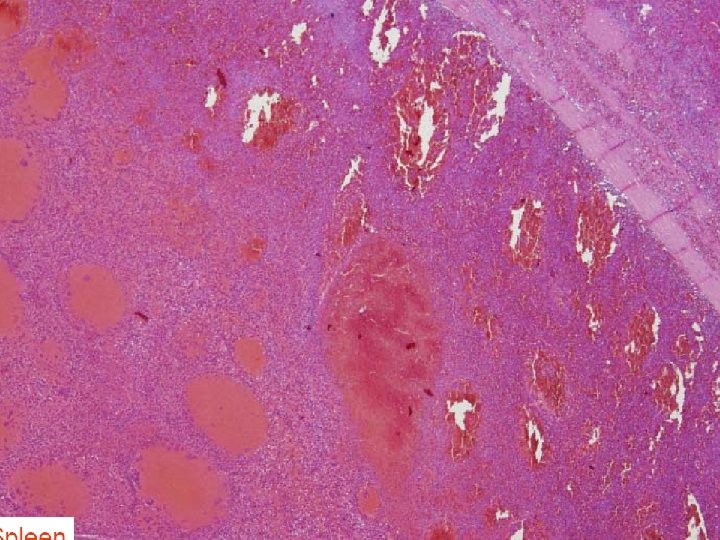

Kemik iliği ve Dalak • Fibrozis nedeniyle genellikle kemik iliği yapmak mümkün olmaz • Biyopside ise etrafı boş alanlarla çevrili yuvarlak veya oval nükleuslu lenfosit infiltrasyonuları görülür(yağda yumurta görünümü) • Retikülin boyası ile retikülin liflerde artış gösterilebilir • Lenfositler dalağın kırmızını pulpasını infiltre ederek atrofiye ve beyaz pulpanın istilasına neden olurlar • Dalakta karekteristik olarak saçaklı hücreler tarafından çevrelenmiş kan dolu başluklar görülür (pseudasinus)